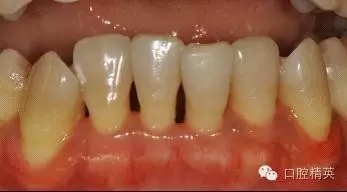

治療后:炎癥得到控制,牙周袋已消除,松動(dòng)度有所改善。

牙周固定后: